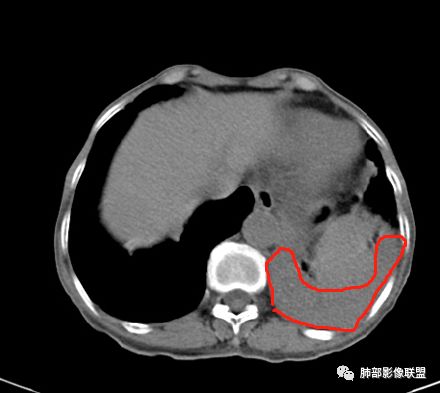

这些应该是胸水

支气管扩张、扭曲成团,附近钙化灶

这例左下叶的体积是整体缩小的,左下叶的支气管主干稍微小一点点,然后左上叶的下舌段也有类似的病灶,然后我们看到一团乱的支气管扩张,但它有特点,边缘凹凸不平。那什么样的支气管扩张边缘会如此凹凸不平呢,等我截个图:

首先这幅图支气管很多地方是扭曲的,远端扩张的特别厉害。如果是肿瘤,首先考虑淋巴瘤,因为支气管可直达远端,稍扩张,但是它的前提是周围要实性占位的,而且它不会这样扭曲变形。我们看这个病例的支气管扩张,它支气管扩张占大部分区域,中间稍有些实性的结构,这就不符合了。这幅图你会发现所有支气管都是扩张的,实性部分偏少,外围胸水。所以我更倾向慢性炎性病变,能够引起支气管扩张的炎性病变有哪些?结核?NTM?支扩伴感染?大方向是慢性炎性病变。这些左下肺播散出来的病灶,咳中等量黄浓痰,我考虑还可能合并细菌感染。

1.双肺斑片影、大小不等结节影,边界不清,密度较均一,钙化不多见,可见树丫。

2.左肺下叶大范围病灶,其间柱状支气管扩张相当显眼。

这些都支持慢性炎性改变。

3.我们知道继发性肺结核为典型的慢性消耗性疾病,较少出现高热及较大量浓痰。该患者病灶密度较均一,新旧不等的特点并不突出,缺少高密度区,双肺上叶比较干净,夸张的支扩也有别于结核病灶导致的“鸡爪样”改变。

4.两次培养出鸟-胞内分枝杆菌,其为致病菌之一当无异议,是否有其他病原菌趁火打劫未能确定。

5.影像学改变可以用非结核分枝杆菌感染解释。

6.我们不能确定的是,该病例支扩与NTM感染之间的先后关系。NTM感染易形成支扩,但支扩是否早已存在,缺乏历史资料比对。